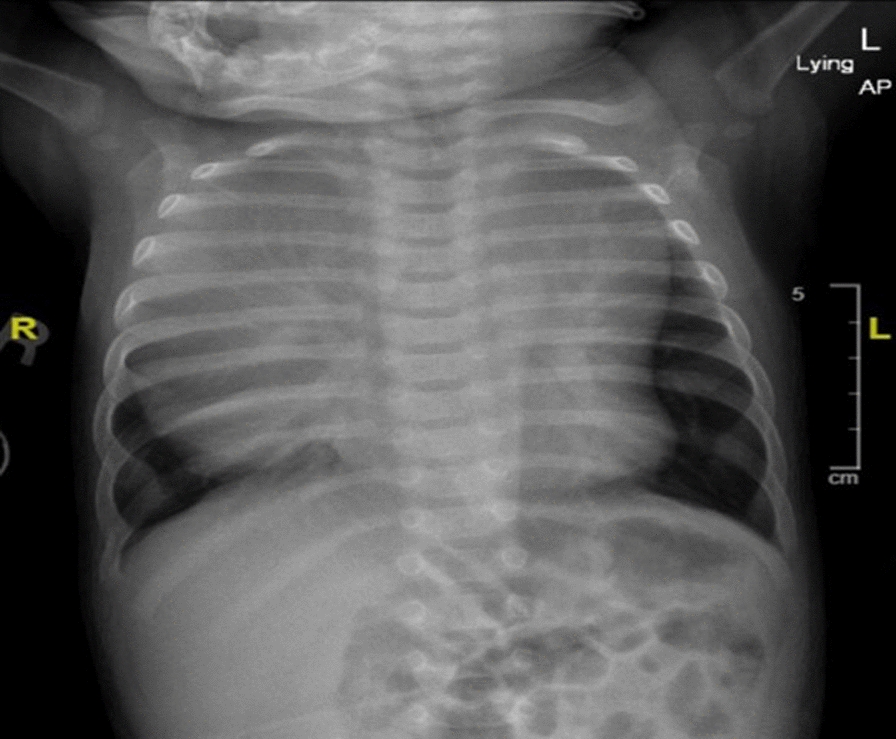

Here we present a 3-month-old Middle Eastern infant weighing 3.2 kg with a large congenital teratoma who presented to the emergency room with cyanosis and respiratory distress. During his hospital course, he underwent three procedures, two of them under light-to-moderate sedation: a diagnostic computer tomography scan followed by mass content drainage by interventional radiology (Figs. 1, 2). On the third day, he had a thoracotomy with complete tumor resection under general anesthesia with the help of an epidural for pain control (Fig. 3). The resected tumor weighed 2.5 kg, which was equal to twice the patient’s total body weight (Fig. 4). After the surgery, he was extubated in the operating room and discharged home 3 days later.

Fig. 1

Anterior–posterior chest x-ray showing the anterior mediastinal mass (AMM)